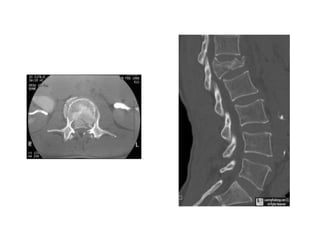

CT Scan

• Accurate assessment

of bone.

1- Comminution.

2- Canal compromise.

3- Dislocation.

• 43.

CT Scan • Accurateassessment of bone. 1- Comminution. 2- Canal compromise. 3- Dislocation.